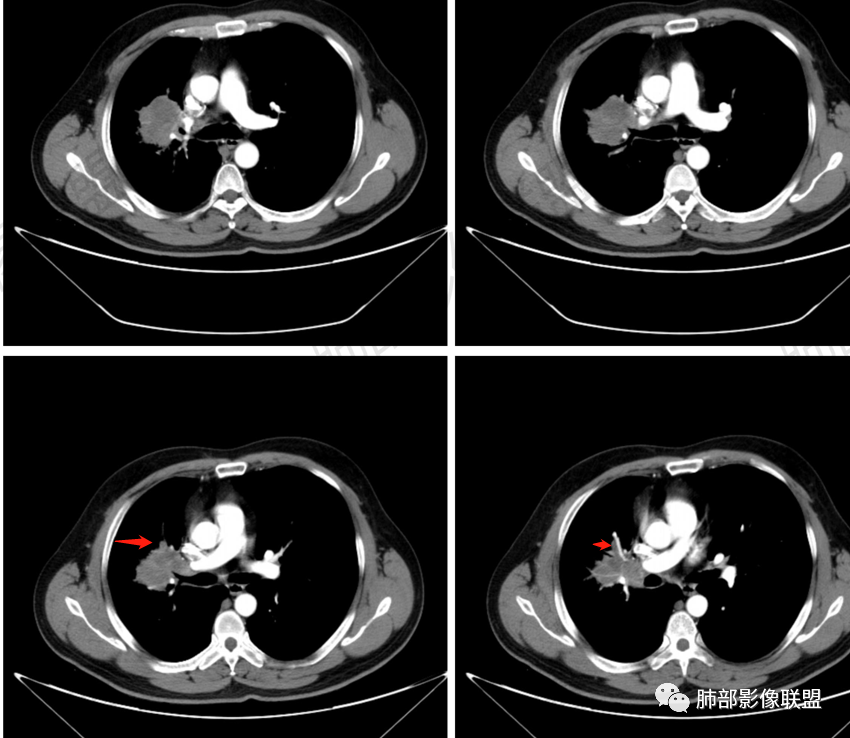

了:中年男性,右肺门肿块影,浅分叶,周围晕征,边缘清楚,小叶间隔增厚,树芽征,支气管截断,不均匀强化,内可见低密度坏死,纵隔淋巴结肿大,综合考虑肺部肿瘤并阻塞性肺炎

一切∮随缘:右肺门肿块影形态不规则,边缘毛糙,右肺上叶支气管堵塞,病变跨叶生长,远端血管束增粗,周围散在多发结节,部分位于胸膜下,平扫密度尚均匀,增强后不均匀强化,呈中度强化,坏死区无强化,纵隔淋巴结肿大。临床无感染症状,考虑恶性,鳞癌,腺癌,鉴别慢性脓肿。

那个人:中年男性,右肺肿块影,支气管截断,截断口非圆盾,病灶膨隆分叶,坏死,强化。病灶内血管破坏。病灶远端树芽及小结节影,考虑恶性,鉴别结核

周太狼:中年男性,吸烟史,陈旧结核史,呼吸道症状未提及,抗感染治疗无效。影像见右上肺门区软组织肿块影,浅分叶、毛刺,支气管似有截断,其内密度不均匀,不均匀强化,内可见低密度坏死区,病壮周围见斑片、结节影。纵隔内淋巴结稍肿大,首先考虑恶性,肺部肿瘤并阻塞性肺炎,肺鳞癌可能,鉴别结核。

弹指之间:中年男性,结核史、吸烟;右肺门肿块,特点:右肺上叶尖、前段支气管狭窄、部分阻塞(肿块大、支气管狭窄闭塞相对轻),肿块内血管部分残留(生长速度快,浸润>破坏),周围见渗出、炎症,部分实变;内见坏死、位于边缘区域;纵隔淋巴结肿大;考虑恶性,1.非支气管粘膜起源首先考虑,淋巴瘤?(但坏死相对多了);2.鳞癌(支气管阻塞轻);3.小细胞待排。

Coke with ice:病变整体收缩平直,毛刺较软,支气管壁增厚。支气管鼠尾状狭窄,于病灶以远可见显示。支气管粘液栓。相邻支气管血管推移明显,磨玻璃边缘模糊,多灶坏死边缘清晰,一部分血管自然穿行,猜个炎性病变。

这个比较大的坏死灶,边缘清晰,看似符合鳞癌坏死。仔细看看这个坏死边界,是血管阻挡引起的边界清晰。其他的病灶内低密度是柱形粘液栓。实性部分强化有轻度延迟强化。病变背景是双上肺的小叶中心结节。病变区的支气管壁是厚的。

右上叶肺门区肿块,较大:

前段支气管鼠尾状狭窄,壁增厚

尖段/后段支气管受压推移

浅分叶,内部坏死部分边界不清,实性部分明显强化

南边:支持恶性,鳞癌首选,结核待排